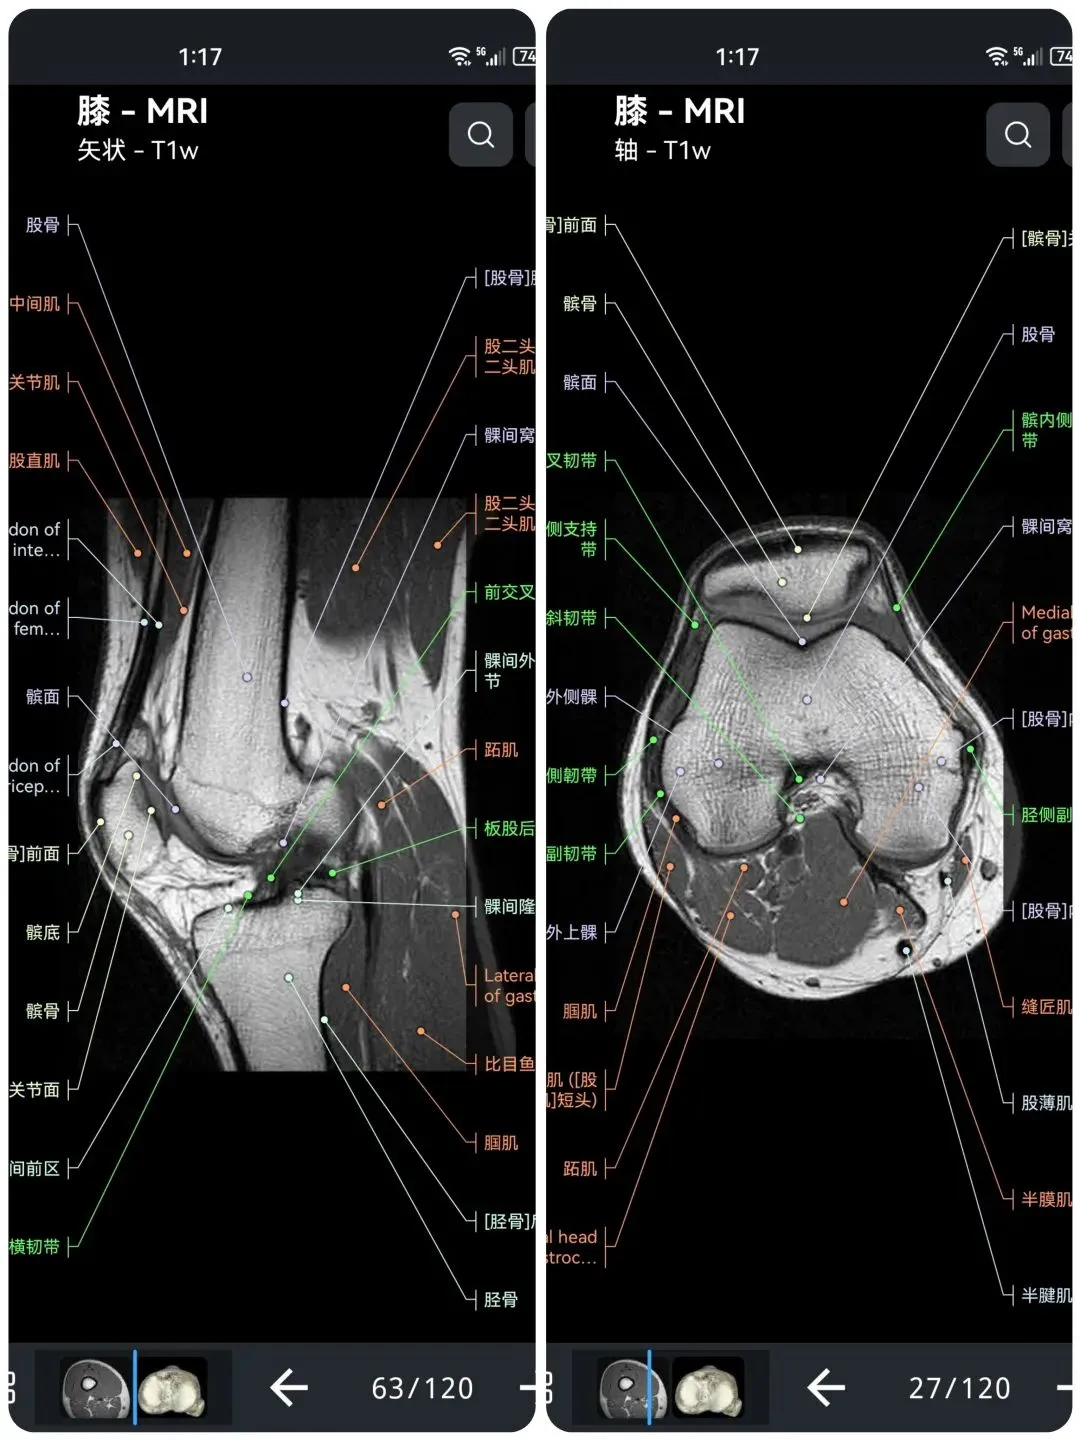

🌈这是国外引进的一款专业影像解剖学习软件。

覆盖了X光、CT、MRI、断层大体解剖、核医学、介入造影、医学插图等多个模块,覆盖全身各个系统的影像解剖(正常解剖结构,无病例),其中的解剖结构高达87万个,结构标注超精细,超高清图像,历时两年研发设计完成✅。

手机端:安卓、华为手机或平板 【推荐】 电脑端:Windows系统;